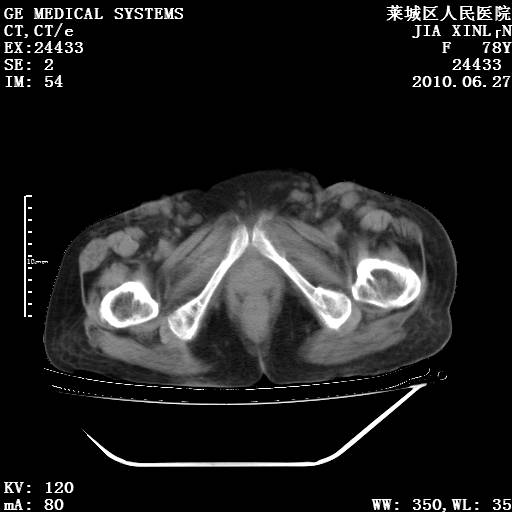

以下是引用胡宇在2010-7-2 19:11:00的发言:[br]神经纤维瘤的特点为:肿块呈多发性、数目不定,少的几个,多的可成百上千难以计数。小的如米粒,大的似拳头,甚至可达十数公斤以上。可松弛地悬挂于皮表,皱褶及松弛可致畸形明显。神经纤维瘤沿神经干的走向生长时呈念珠状,或蚯蚓块状形结节。此外神经纤维瘤皮肤可出现咖啡斑,大小不一,形如雀斑小点状,或大片状,分布与神经纤维瘤肿块的分布无关。肿瘤数目不多的患者,皮肤色素咖啡斑状沉着是纤维神经瘤的重要诊断之一。 本病多发于躯干,有时出现于四肢及面部,患者常合并许多疾病应予重视加以区别。 [br] [br] [br] [br]lyb999说 [br]